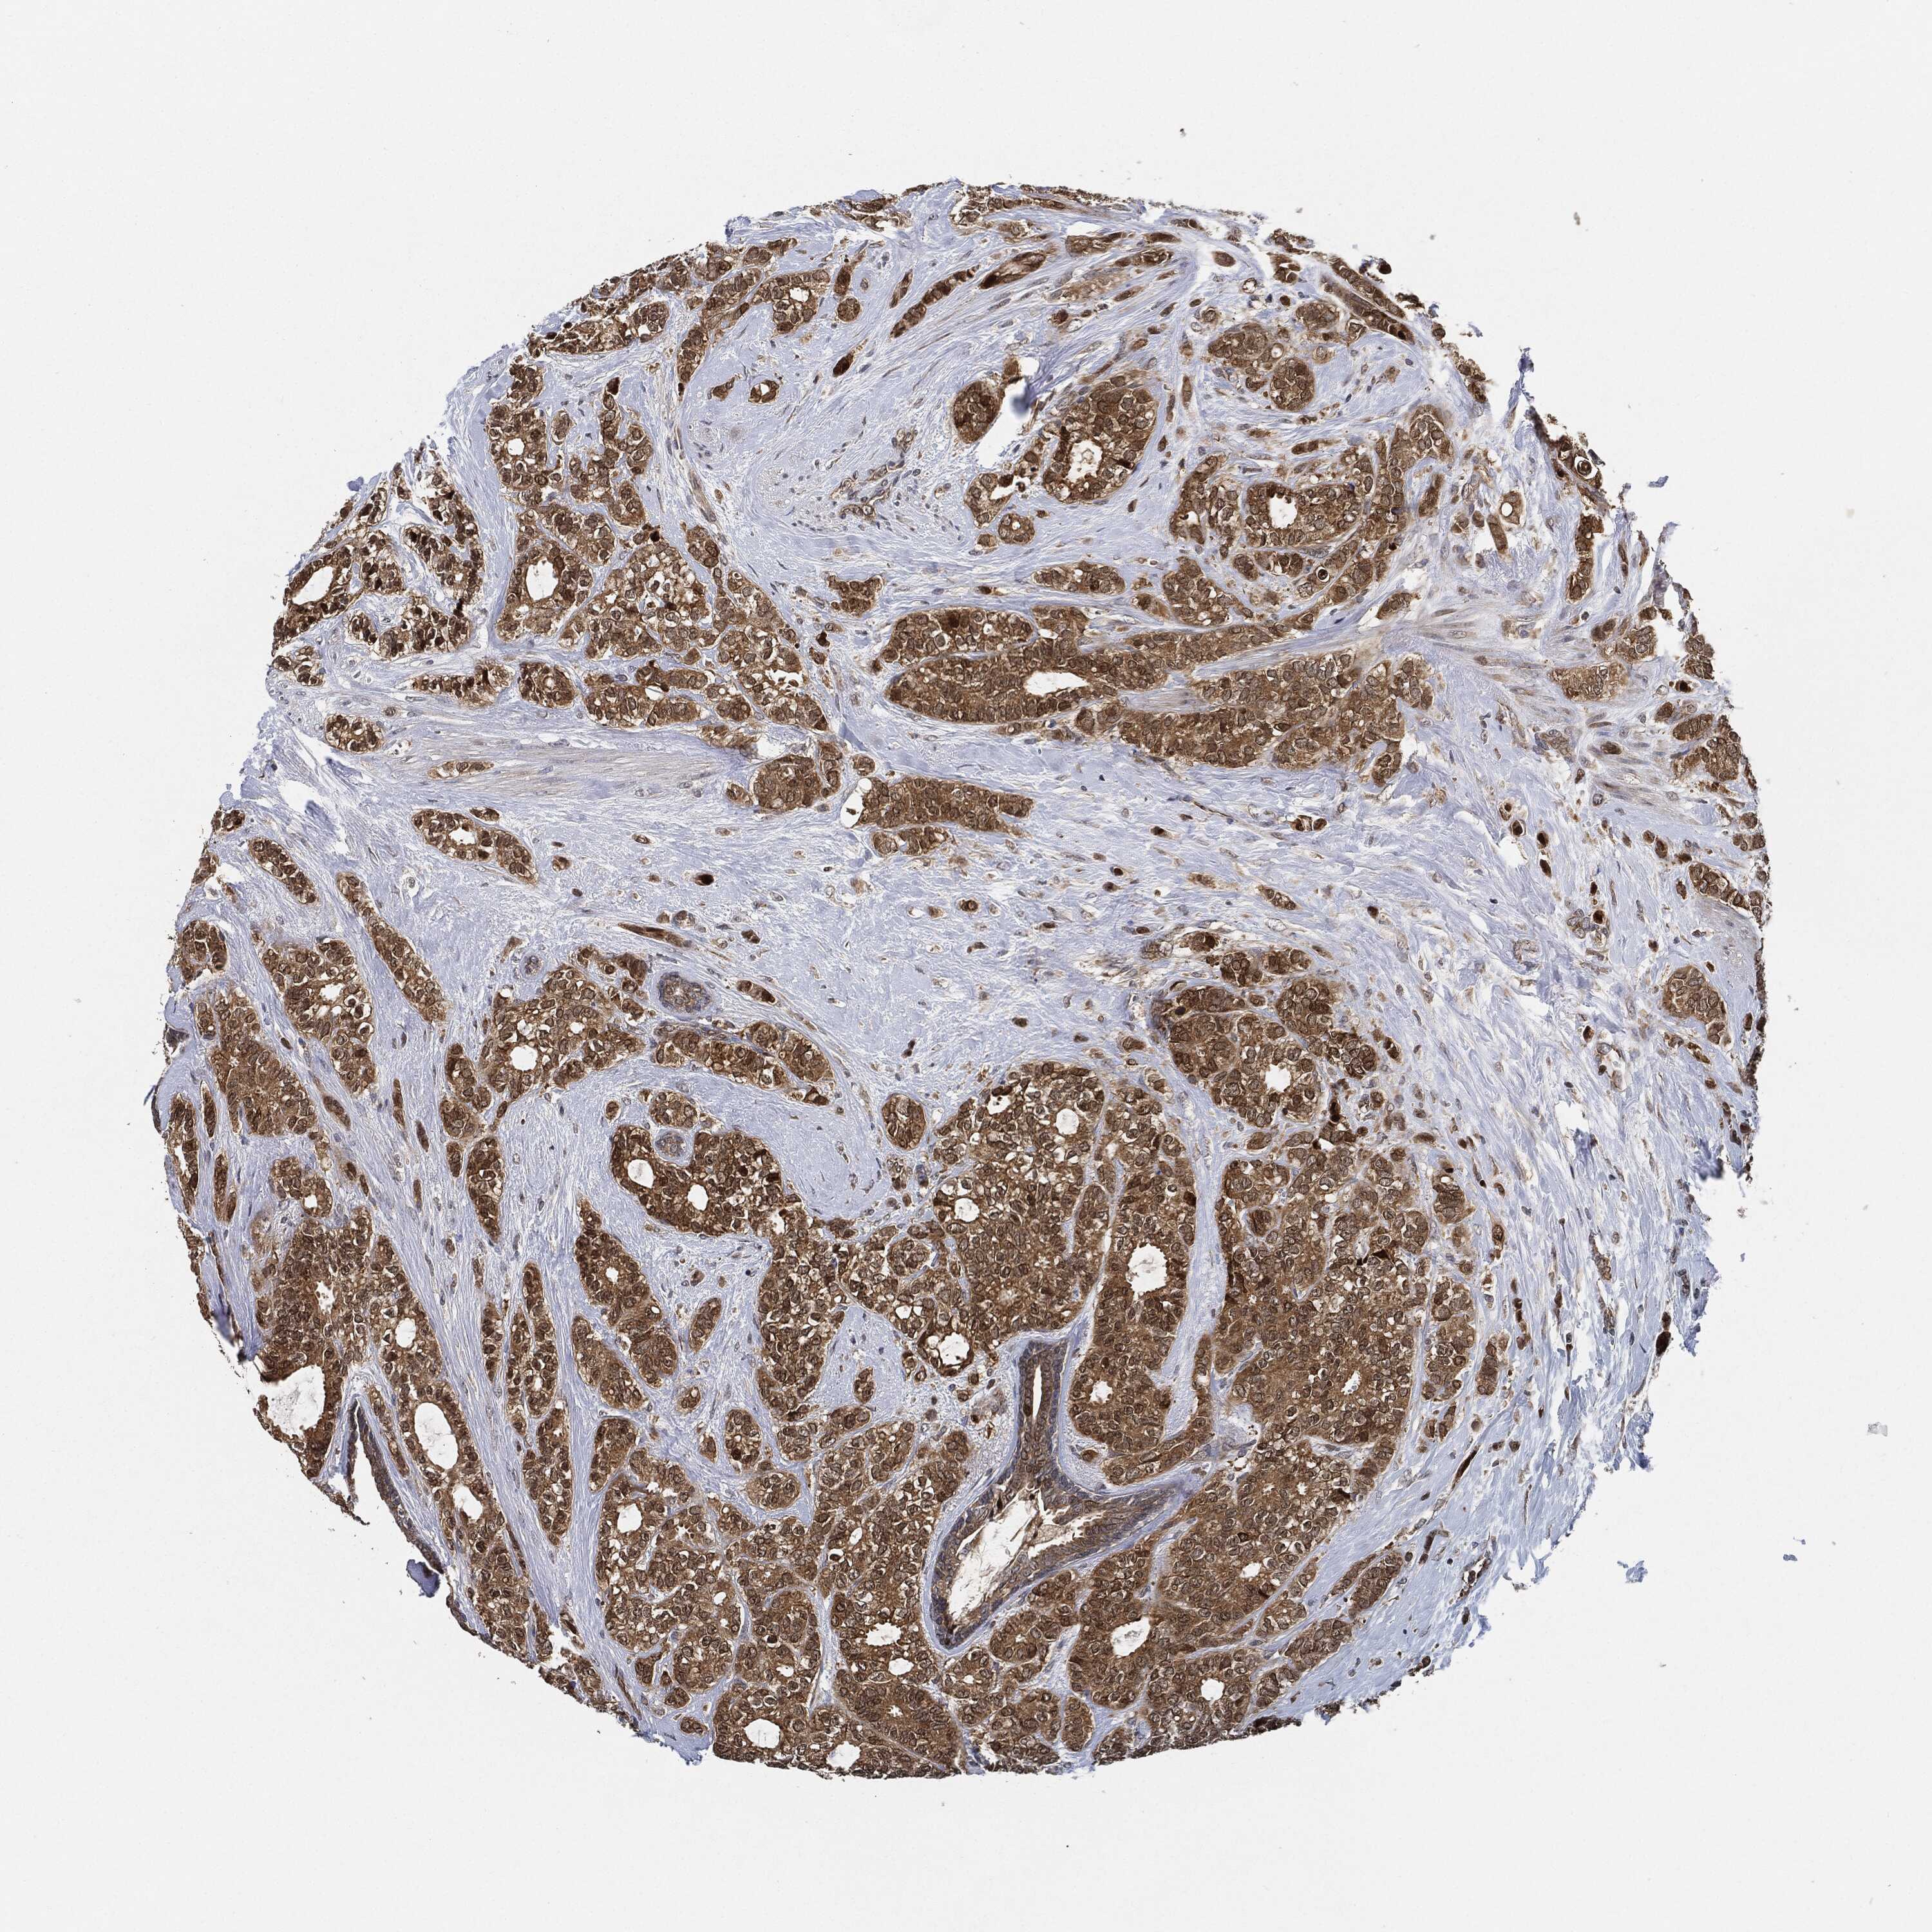

CANCER BREAST CANCER Show tissue menu

BRCA TCGA BRCA VALIDATION PROTEIN EXPRESSION